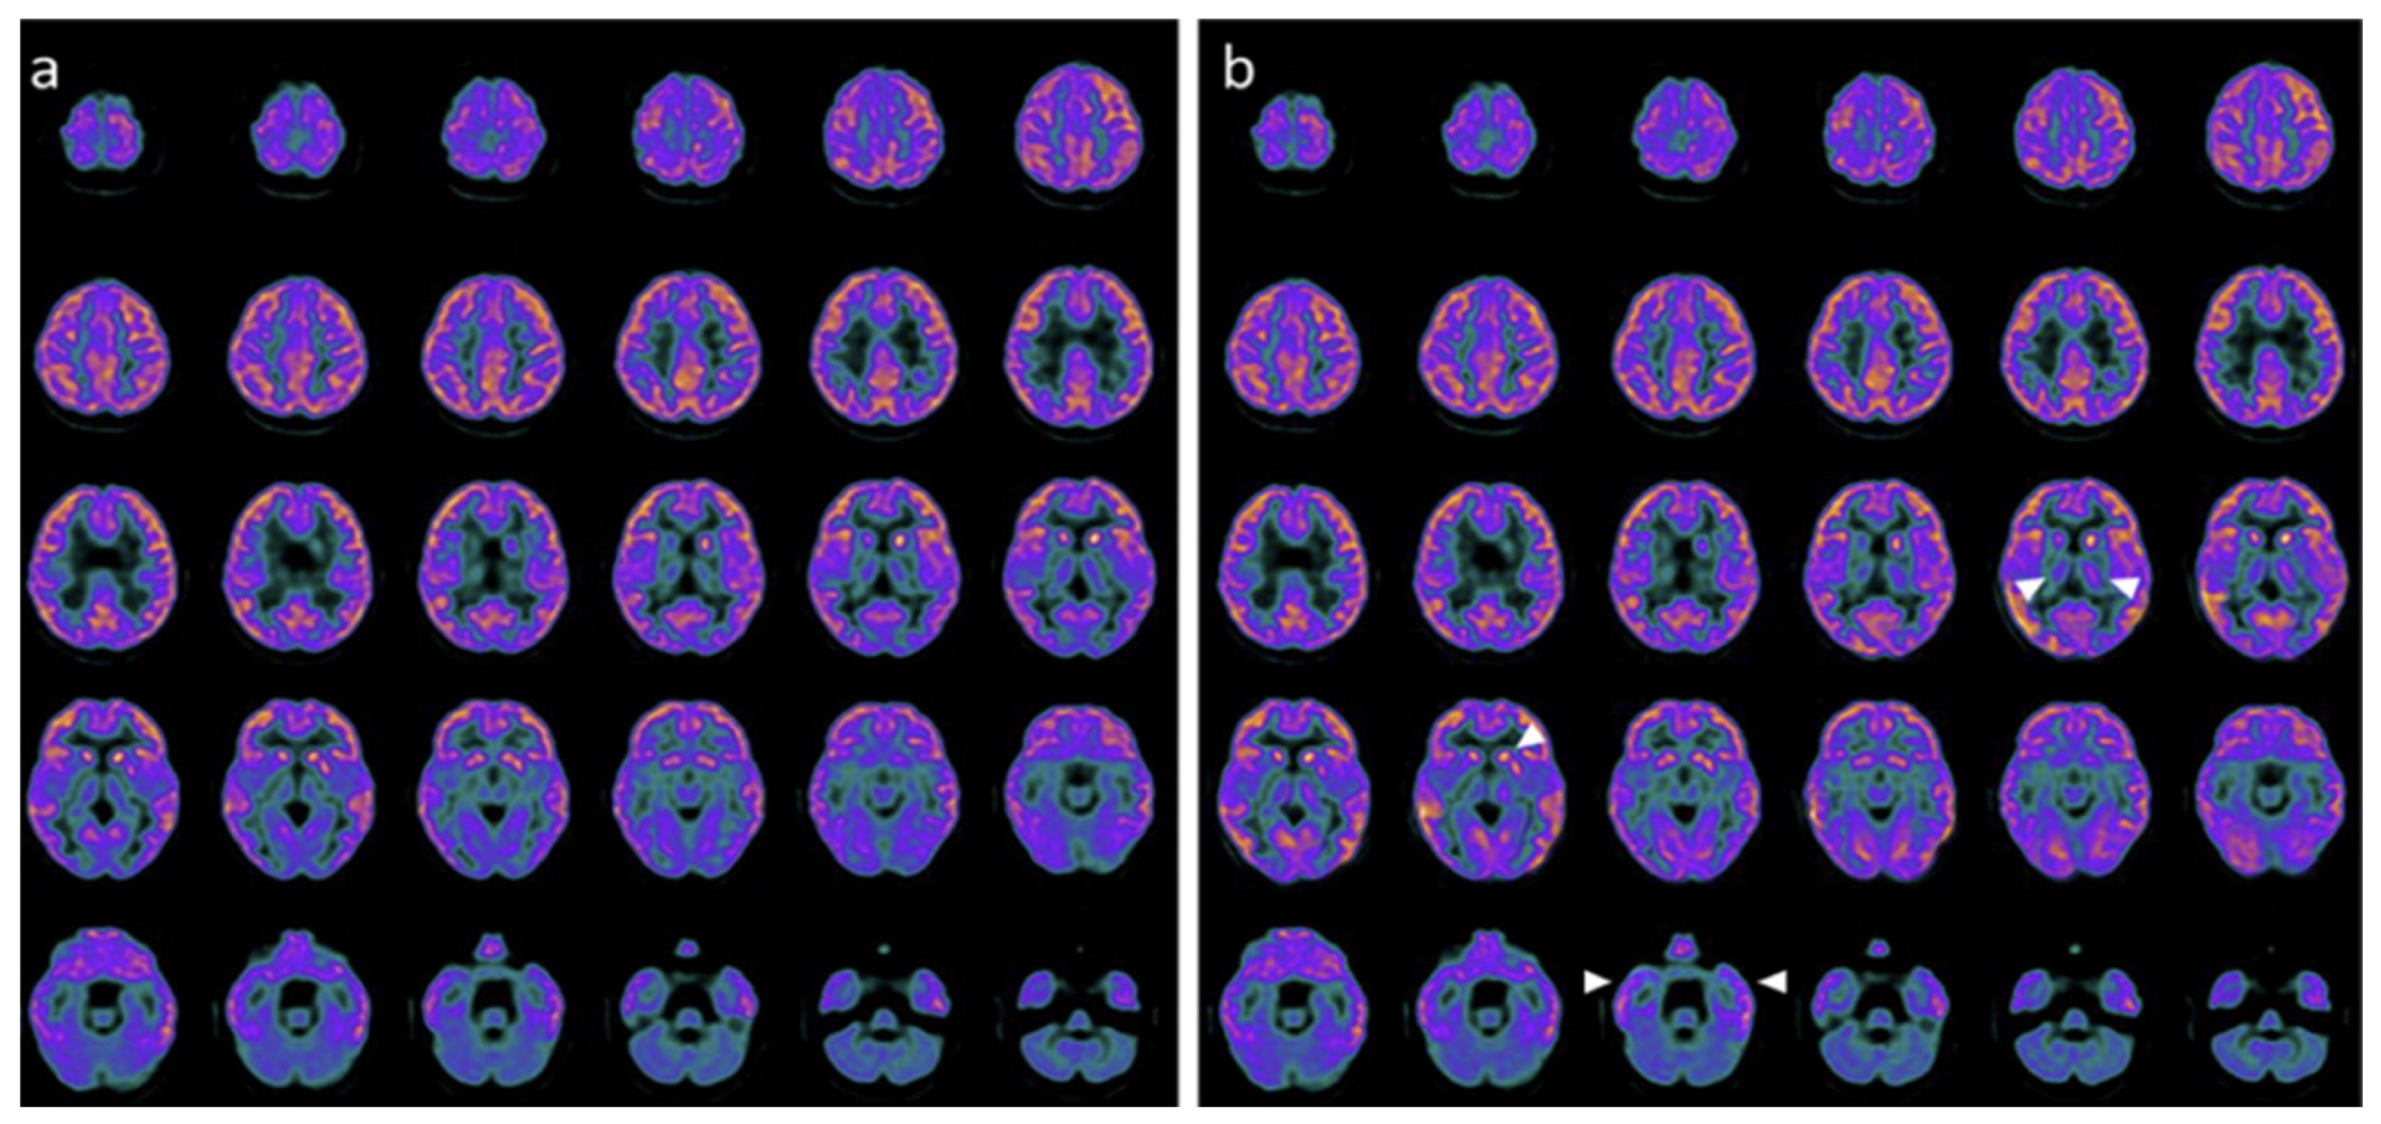

Following combined hr-NGF and tDCS therapy, all patients showed improvements in functional neuroimaging and electrophysiological measures, with PET and SPECT demonstrating increased metabolic activity and perfusion in previously hypoactive regions, and EEG/PSD analyses indicating more organized cerebral electrical activity (Figure 8) [31].

Figure 8. In the three HIE patients, the topographical analysis of the post-treatment EEG PSD distribution revealed a reduction in slow-frequency delta and theta bands—typically predominant in severe brain dysfunction—a milder decrease in the alpha band, and an increase in fast beta activity, usually associated with active thinking, concentration, and alert wakefulness. The observed spectral power shift from low-frequency (slow) to high-frequency (fast) bands may represent a neurophysiological marker of restored cerebral reactivity and a potential sign of clinical improvement.